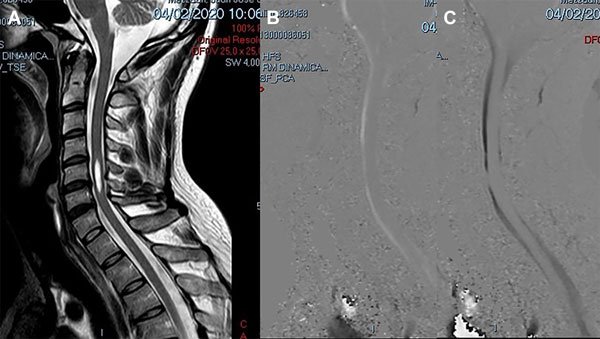

Un varón de 38 años de edad consultó por haber padecido una cérvico braquialgia derecha 30 días antes. En el momento de la consulta sus síntomas habían desaparecido y el examen neurológico fue normal. La RM mostró discopatías cervicales múltiples con una dilatación quística en la médula cervical a nivel C5-C6 que no tomaba el contraste con gadolinio (Figura 6A). Para profundizar el diagnóstico diferencial se realizó una RM en contraste de fase para medir la velocidad del LCR a nivel del canal cervical. La velocidad medida fue de 11 cm/seg (Figura 6B-C). Se hizo el diagnóstico de SM espinal primaria causada por una discopatía cervical a nivel C5-C6. Como el paciente estaba asintomático sólo se indicó control periódico. En su última evaluación, 2 años después, la situación clínica e imagenológica no había cambiado por lo que se mantuvo la misma conducta.

Figura 6: Caso 4. A: RM de columna cervical en plano sagital ponderada en T2 que muestra una cavidad intramedular entre C5 y C6 compatible con siringomielia. B: Estudio de dinámica de LCR que muestra una imagen de magnitud en fase anterógrada con señal hiperintensa el flujo en sístole con disminución del pasaje del LCR en C5-C6. C: Estudio de dinámica de LCR que muestra una imagen de magnitud en fase retrógrada con señal hipointensa el flujo en diástole con la alteración del pasaje de LCR a nivel C5-C6.